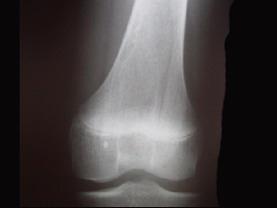

问题 病例,女,15岁,因感右股骨下段不适,不痛不胀,体查无特殊,请结合所提供的图像,选择最佳选项是 ( )

选项 A、良性骨肿瘤 B、骨结核 C、非骨化性骨纤维瘤 D、骨囊肿 E、纤维性骨皮质缺损

答案 E